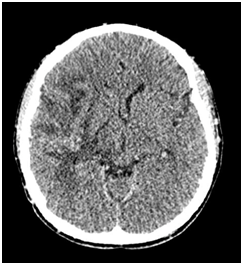

We present the case of a 16-year-old male patient, born in Veracruz Mexico with history of pulmonary stenosis, hypoplastic right ventricle, interauricular communication and patent ductus arteriosus who had surgical intervention with Blalock Taussig shunt on November of 2003. On July 11th 2016 he started with numbing of the left half of his face including the tongue, for which he didn’t seek any medical attention. On July 18th 2016 he had a generalized seizure, which lasted 10 minutes, according to his family. On July 28th 2016 he started to lose strength of the left half of his body and wasn’t able to walk or move his left arm. With these symptoms he was admitted to our hospital where he also referred headache. CT scan showed hypodense images on right temporoparietal region and reinforcement images on right parietal region suggesting brain abscesses (Figure 1 & 2). With these findings, along with the clinical presentation, the diagnosis of brain abscess was made and antibiotic treatment was started with third generation cephalosporin, metronidazole and glucopeptide. The patient was evaluated by the neurosurgery team who decided to differed surgical treatment because of the size of lesions in CT scan and improvement in next CT scan images. On August 8th 2016 a MRI (Figure 3) of the brain showed capsule formation. The patient continued with antibiotic treatment and dexamethasone in reduction dose. A new MRI of the brain, on August 29th 2016, showed abscesses of less than 3 cm, this along with the patient improving neurological state and decide no need for surgical treatment. The patient completed 61 days of parenteral treatment with ceftriaxone, metronidazole and vancomycin. The last imaging study previous to the discharge of the patient showed brain abscesses of less than 0.5 cm.

Figure 2